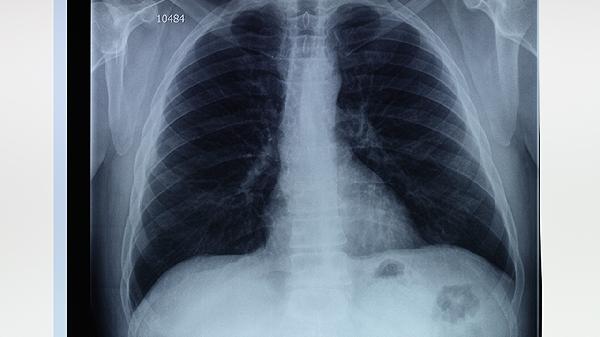

肺大泡病人可通过戒烟、药物治疗、氧疗、手术治疗、呼吸康复训练等方式改善病情。肺大泡通常由长期吸烟、慢性阻塞性肺疾病、肺部感染、遗传因素、外伤等原因引起。

对于巨大肺大泡或反复发生气胸的病人,可考虑手术治疗。胸腔镜下肺大泡切除术创伤小、恢复快;开胸肺大泡切除术适用于复杂病例。术后要注意呼吸功能锻炼,预防肺部感染。手术可有效消除肺大泡,但无法根治基础肺疾病。